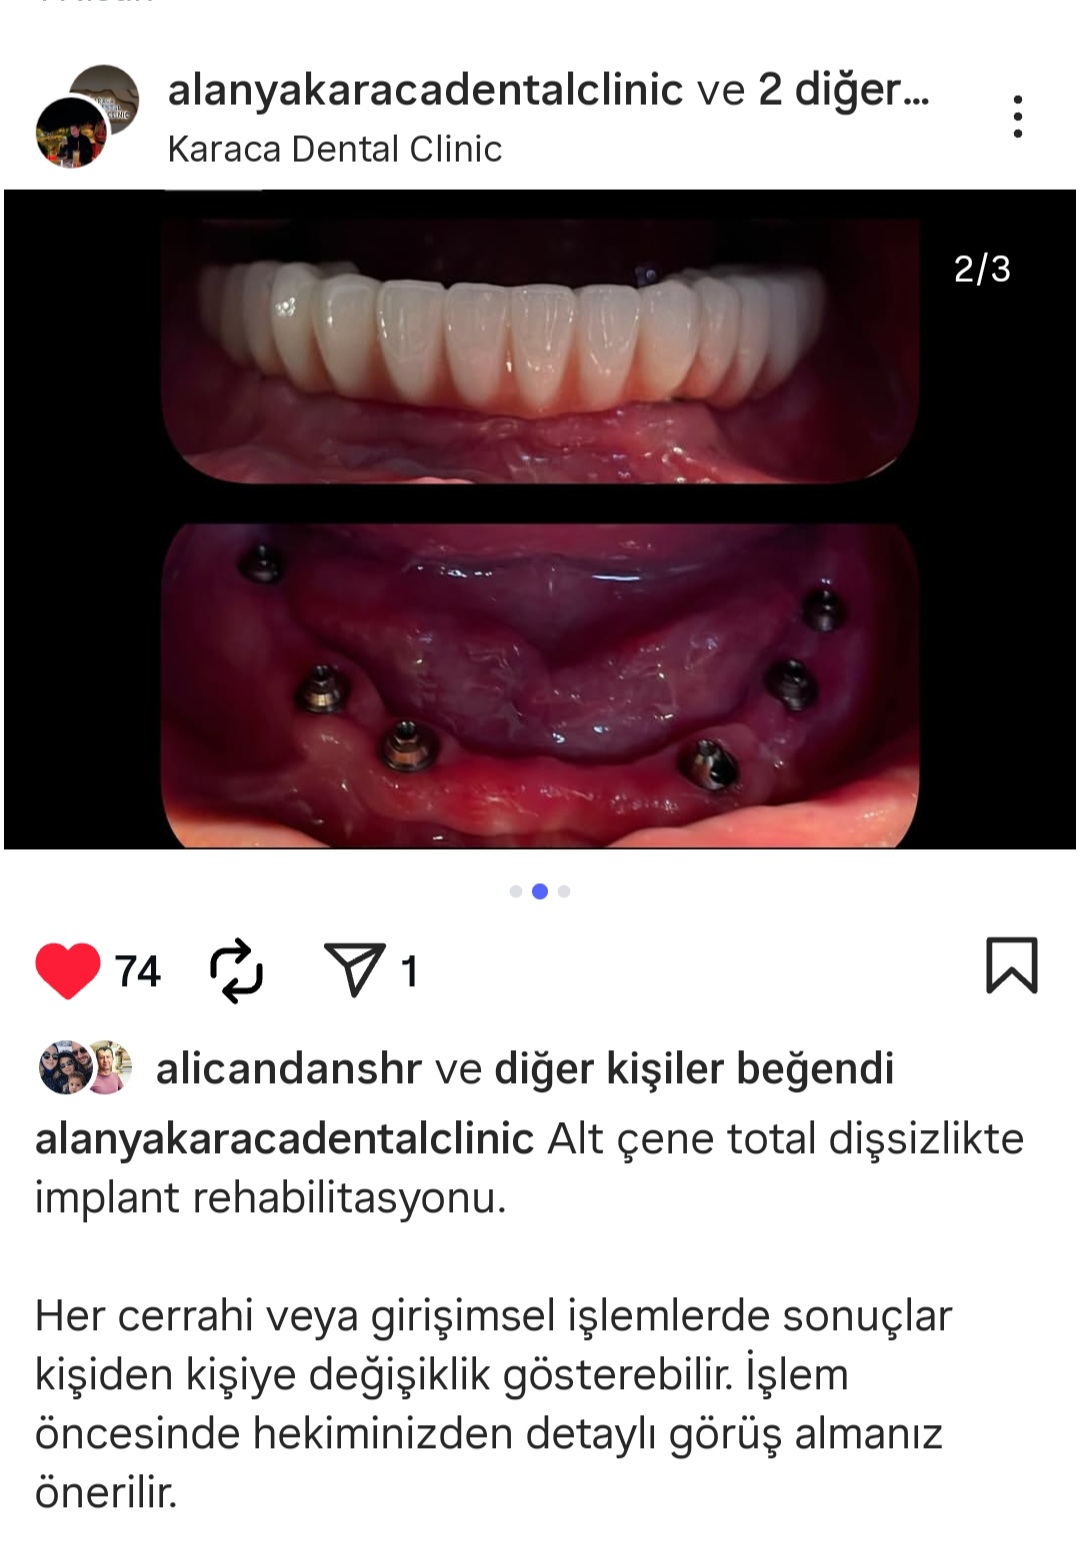

- Diş Dolgusu Kanal Tedavisi İmplant Tedavisi Çocuk Diş Hekimliği (Pedodonti) Lamina Kron Kaplama Zirkonyum Kron Kaplama Estetik Dolgu Estetik Gülüş Tasarımı Hollywood Gülüşü Diş Taşı Temizliği Air Flow Diş Temizleme Diş Beyazlatma Diş Çekimi Gece Plağı Dijital Diş Hekimliği 7/24 Diş Kliniği Hizmeti Acil Diş Kliniği Hizmeti Nöbetçi Diş Kliniği Hizmeti # HİZMETLERİMİZ #